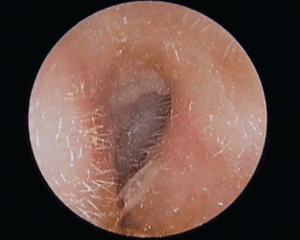

Diagnostika. Otoskopuojant matyti paburkusi, paraudusi išorinė klausomoji landa. Jei procesas ypač aktyvus, galime net nematyti landos spindžio, būgnelis dažnai būna paraudęs, sustorėjęs. Landoje stebimos klampios, dvokiančios išskyros.

Pav. Gydymas. Gydant išorinį otitą būtina kruopščiai išvalyti išorinę klausomąją landą. Jei landos spindis siauras dėl ryškios edemos, rekomenduojama iš pradžių taikyti marlinius tamponėlius, suvilgytus susp. hydrocortisoni, antibiotikų ar priešgrybeliniu tepalu priklausomai nuo sukėlėjo rūšies. Dažniausiai naudojami tepalai turintys savo sudėtyje aminoglikozidų (neomicino – Ung. Baneocin) arba antibiotiko ir kortikosteroido mišiniai (ung. Flucinar, ung. Fucicort). Tamponėlį reikėtų keisti kas 24–48 valandas. Vėliau, atslūgus landos paburkimui, į ausį galima lašinti antibiotikų tirpalus (fluorochinolonų grupės- Ciloxan 0.3%, sudėtinių antibiotikų ir kortikosteroidų lašus- Maxitrol, Dexona), taikyti lazerioterapiją. Jei uždegimas palietė vidurinę ausį ir vietinis antibiotikų poveikis per silpnas, vangi ligos eiga, uždegimas užtruko, pasikartojo po prieš taikyto vietinio gydymo rekomenduojama skirti sisteminius antibiotikus. Taip pat svarbu paskirti stiprius skausmą malšinančius preparatus, nes skausmas esant išoriniam ausies uždegimui – pagrindinis ir nemaloniausias nusiskundimas.